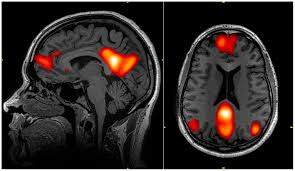

실제로 뇌 과학자 마커스 라이클은 아무 생각도 하지 않을 때, 뇌의 활동에 관한 흥미로운 논문을 발표했다. 그는 아무 일도 하고 있지 않을 때 활성화되는 뇌의 부위를 발견했으며, 이런 뇌의 활동을 ‘디폴트 모드 네트워크(Default mode network)’라 칭했다. 디폴트 모드는 아무것도 하지 않고 쉬고 있을 때만 작동하는 것이 특징이며, 평소에는 분리돼 있는 뇌의 각 부분을 연결하여 창의적인 생각이나 통찰력을 만들어주는 역할을 하는 것으로 밝혀졌다.

dmn.jpg